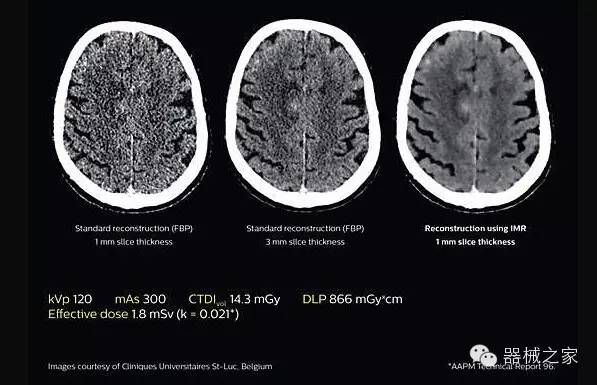

透過數字化影真芯片DAS系統、球面微平板探測器技術和濾線柵技術等硬件技術,整體提高探測器成像的能力,奠定低劑量條件下高清成像的基礎;

應用目前業(yè)界領先的新一代星光平臺iDose4 Premium及基于迭代基礎的O一MAR去除金屬偽影技術,達成微量輻射下零偽影的高清晰成像;

2.腦部顯影